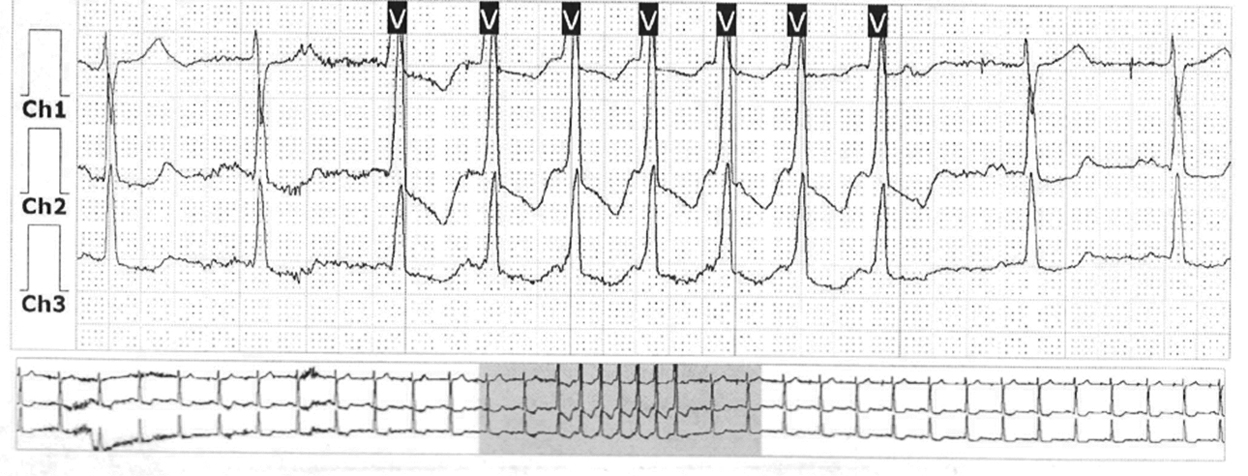

During therapy, the patient’s condition improved significantly, and the dyspnea stopped. Rhythm disturbances persisted as rare non-sustained atrial tachycardia and VT. The maximum well-tolerated daily dose of valsartan and sacubitril did not exceed 200 mg when titrated, and persistent hypotension occurred when further increases were attempted. The patient was then seen in May 2022, and an ECG was performed (Fig. 1).

Fig. 1. Patient’s ECG in May 2022 (recording speed is 50 mm/s)

During Holter ECG monitoring, 73 (0.1%) PVCs, 1 run of non-sustained VT (Fig. 5), 792 (1.0%) atrial premature complexes, and 1 run of non-sustained atrial tachycardia were recorded. The dynamics of the number of ventricular and atrial rhythm disturbances are presented in Table 4.

Fig. 5. Fragment of ECG monitoring. Episode of non-sustained ventricular tachycardia